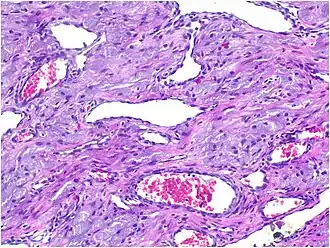

Histopathological Characteristics

Histopathologically, congenital epulis is usually characterized by the presence of big, rounded cells that fill the mucosa's lamina propria and have round to oval nuclei and an abundance of eosinophilic cytoplasm.[10] A thin layer of connective tissue separated the surface layer of cells from the growing new cells. Numerous histological traits, such as a fibrous and granulomatous appearance, have been reported in recent research.[10]

Microscopically, congenital epulis is composed of:

- Sheets of proliferating polygonal to round cells with overlying thin squamous, eosinophilic, granular cytoplasm[12][13]

- Centrally located, round nuclei [7]

These histopathological features are essential in distinguishing congenital epulis from other gingival and soft tissue neoplasms.